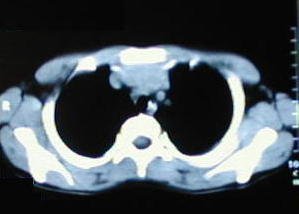

Tomografía de tórax

• Corte tomografico a nivel del tercio superior del torax, supracarinal.

• Corte tomografico a nivel carinal, comienza a insinuarse la depresión esternal.

• A medida que descienden los cortes, se observa la mayor depresión esternal.

• A nivel del tercio inferior se observa el punto de máxima depresion esternal.

• Corte a nivel del apéndice sifoides, observe la acentuada depresión por efectos de los cartilagos costales comunes.

• A nivel de la base del tórax los extremos de los arcos costales se observan protruyentes, debido al cambio de dirección de los cartílagos, ellos generalmente ceden, al resecar los cartílagos costales comunes.